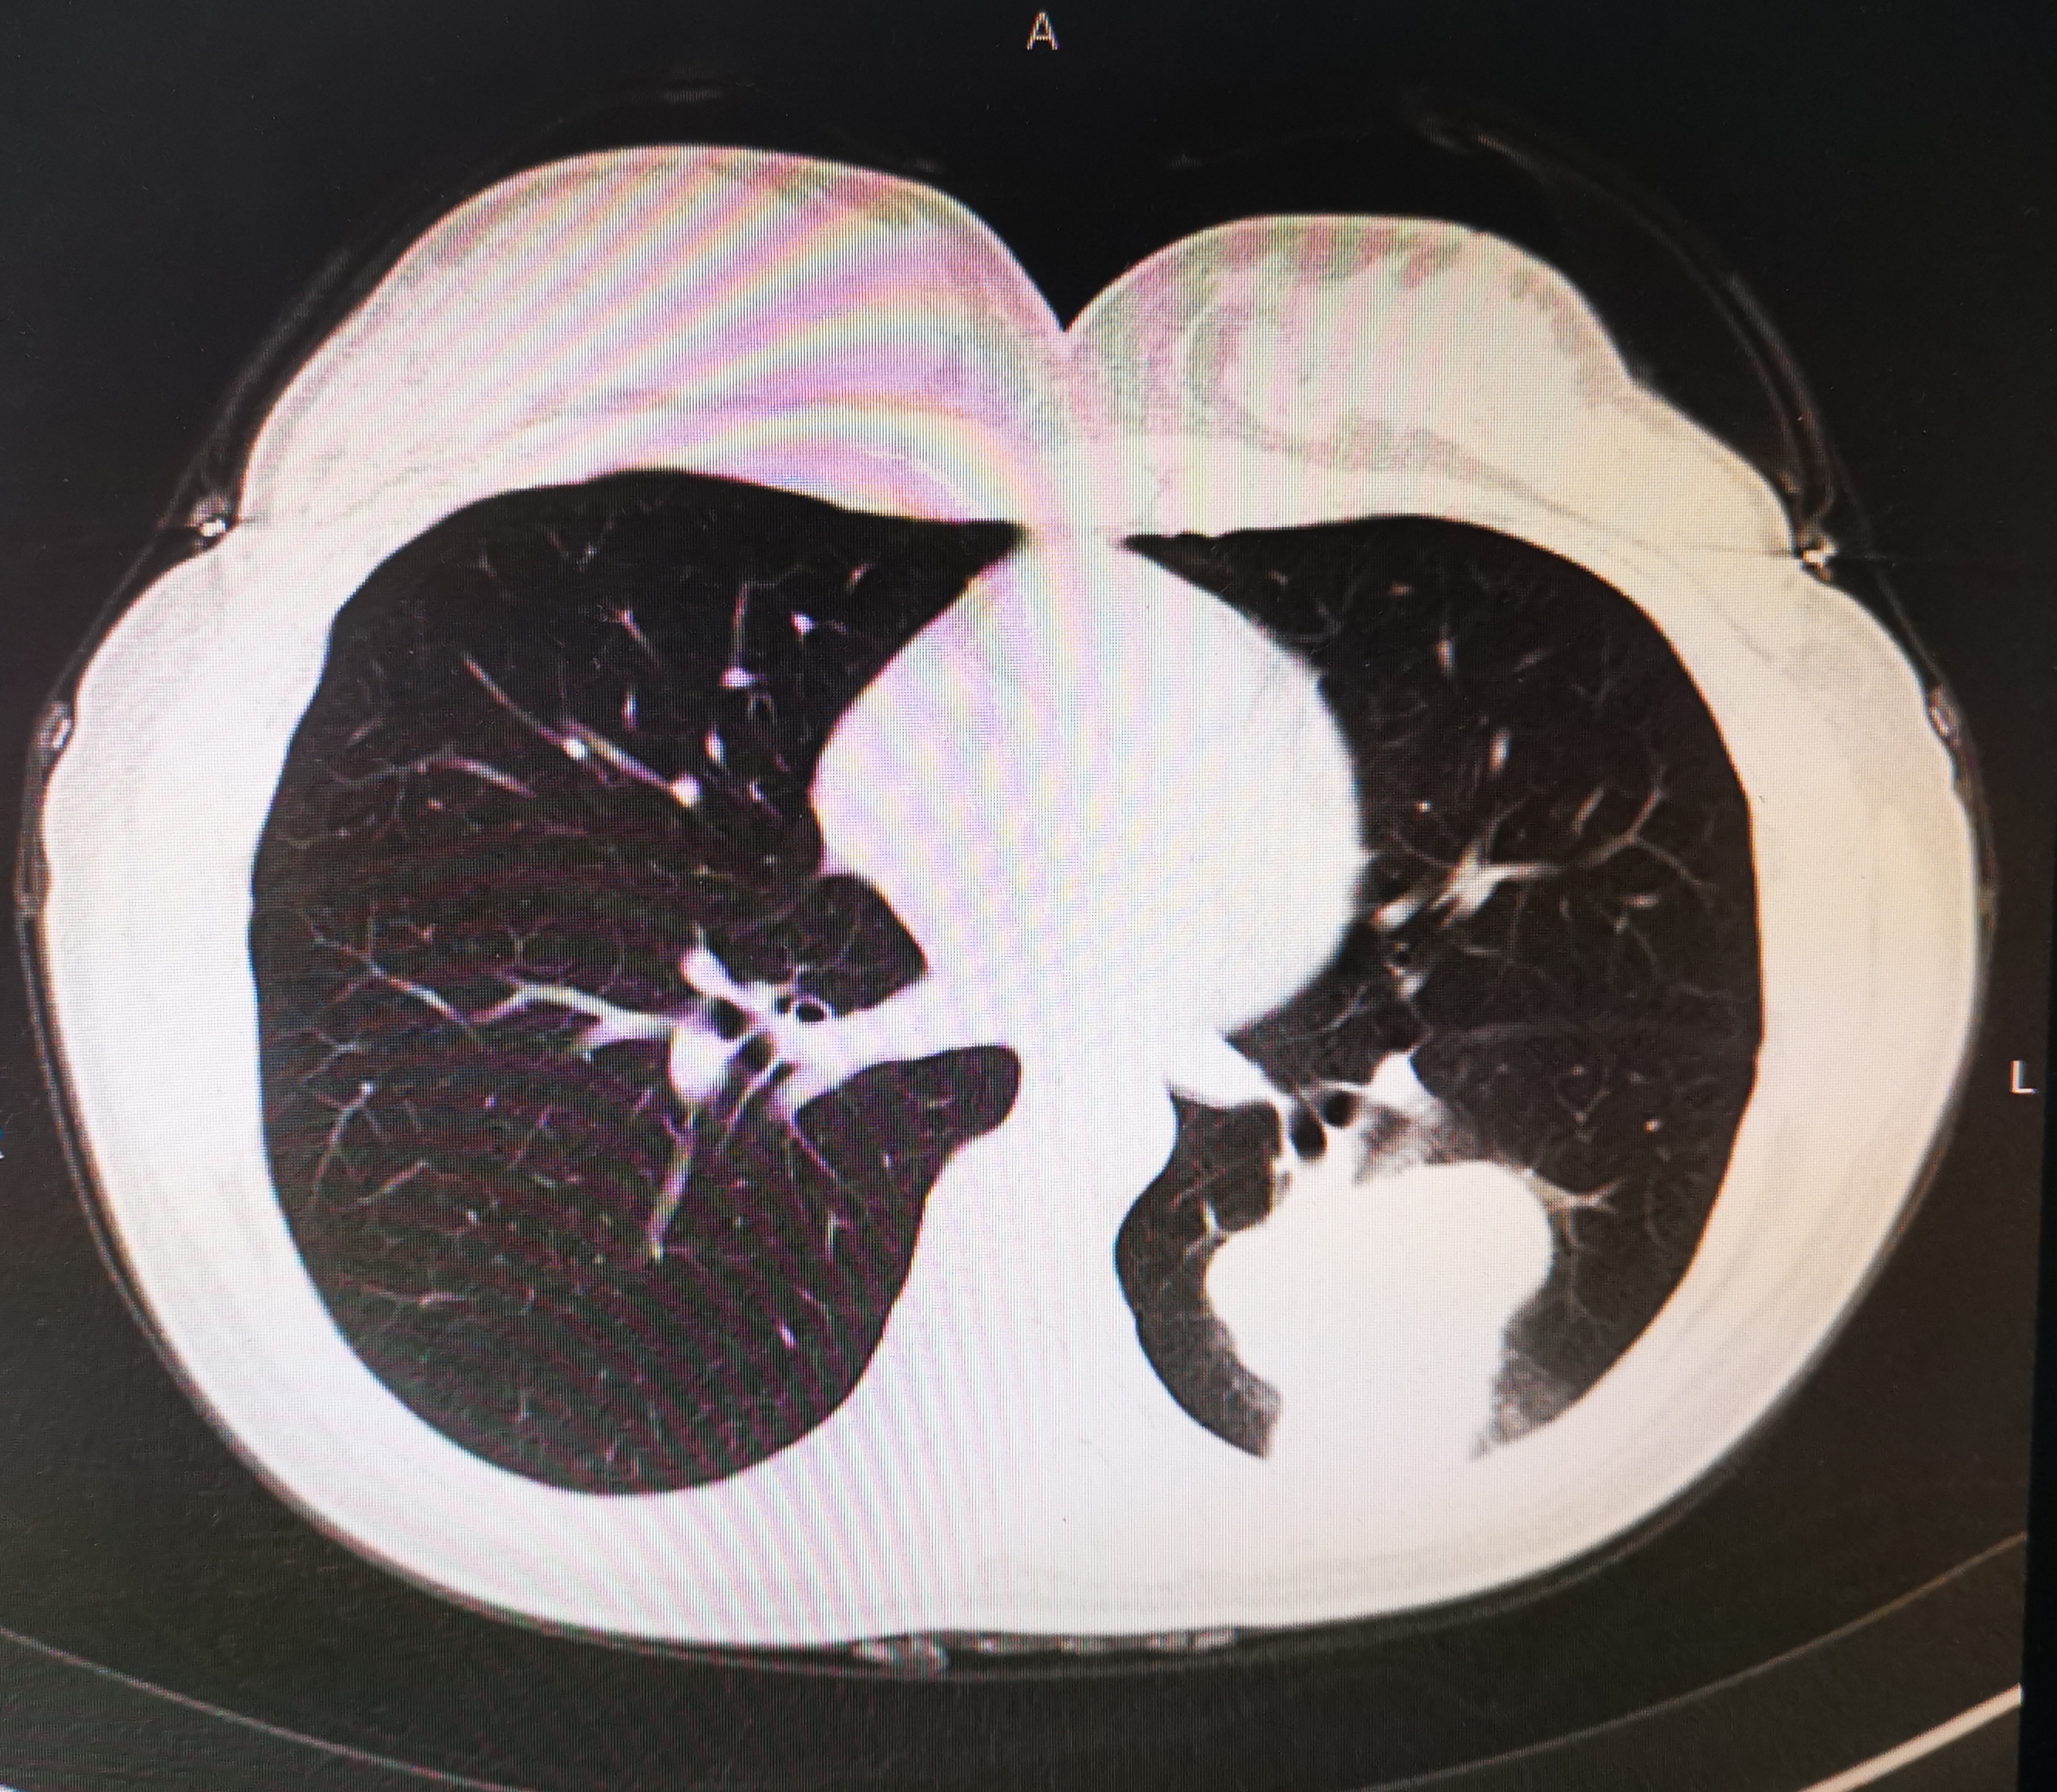

我马上调出她的病历,原来去年12月份她就发现了肺癌,已经化疗了一次,因为耐受性差,一直没继续治疗,现在三个月过去了,出现了颅脑症状。

肺癌图片

肺癌图片 脑转移图片

肺癌是发病率最高的恶性肿瘤,预后不佳,尤其年轻患者,若发现较晚,往往预后更差。那么肺癌应该如何早期发现并诊治呢?希望下面的介绍为大家带来帮助。

原发性支气管肺癌,简称肺癌,起源于气管、支气管粘膜或腺体,是最常见的肺部原发性恶性肿瘤。根据病理组织学,可分为非小细胞肺癌和小细胞肺癌。其中非小细胞肺癌主要包括腺癌和鳞癌。不同类型肺癌治疗不同,预后也有差异。